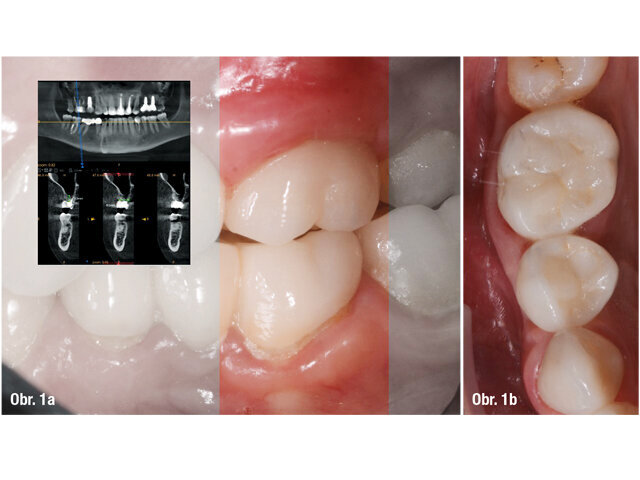

V listopadu roku 2017 se dostavila 39letá pacientka na vstupní vyšetření do White Clinic z důvodu bolesti zubu 16. Bylo provedeno klinické a radiografické vyšetření, včetně periapikálního snímku, CBCT skenu (Carestream 9600, Carestream Dental) a intra a extraorálních fotografií (obr. 1–3).

Při klinickém a radiografickém zhodnocení bylo zjištěno, že u zubu 16 byla přítomna cervikální resorpce v meziobukálním kořeni. Zvolený léčebný plán byl extrakce zubu a okamžité zavedení implantátu. Zub byl již v minulosti endodonticky přeléčen a ošetřen definitivní keramickou korunkou. Přestože je protokolem White Clinic zachovávání zubů, zub byl indikován k okamžité extrakci vzhledem ke stavu v dané situaci. Také z důvodu nedostatku času, nebyl náš digitální tým schopen vyrobit chirurgickou šablonu pro zavedení implantátu, proto zahrnoval léčebný plán chirurgickou fázi a digitální protetickou fázi.